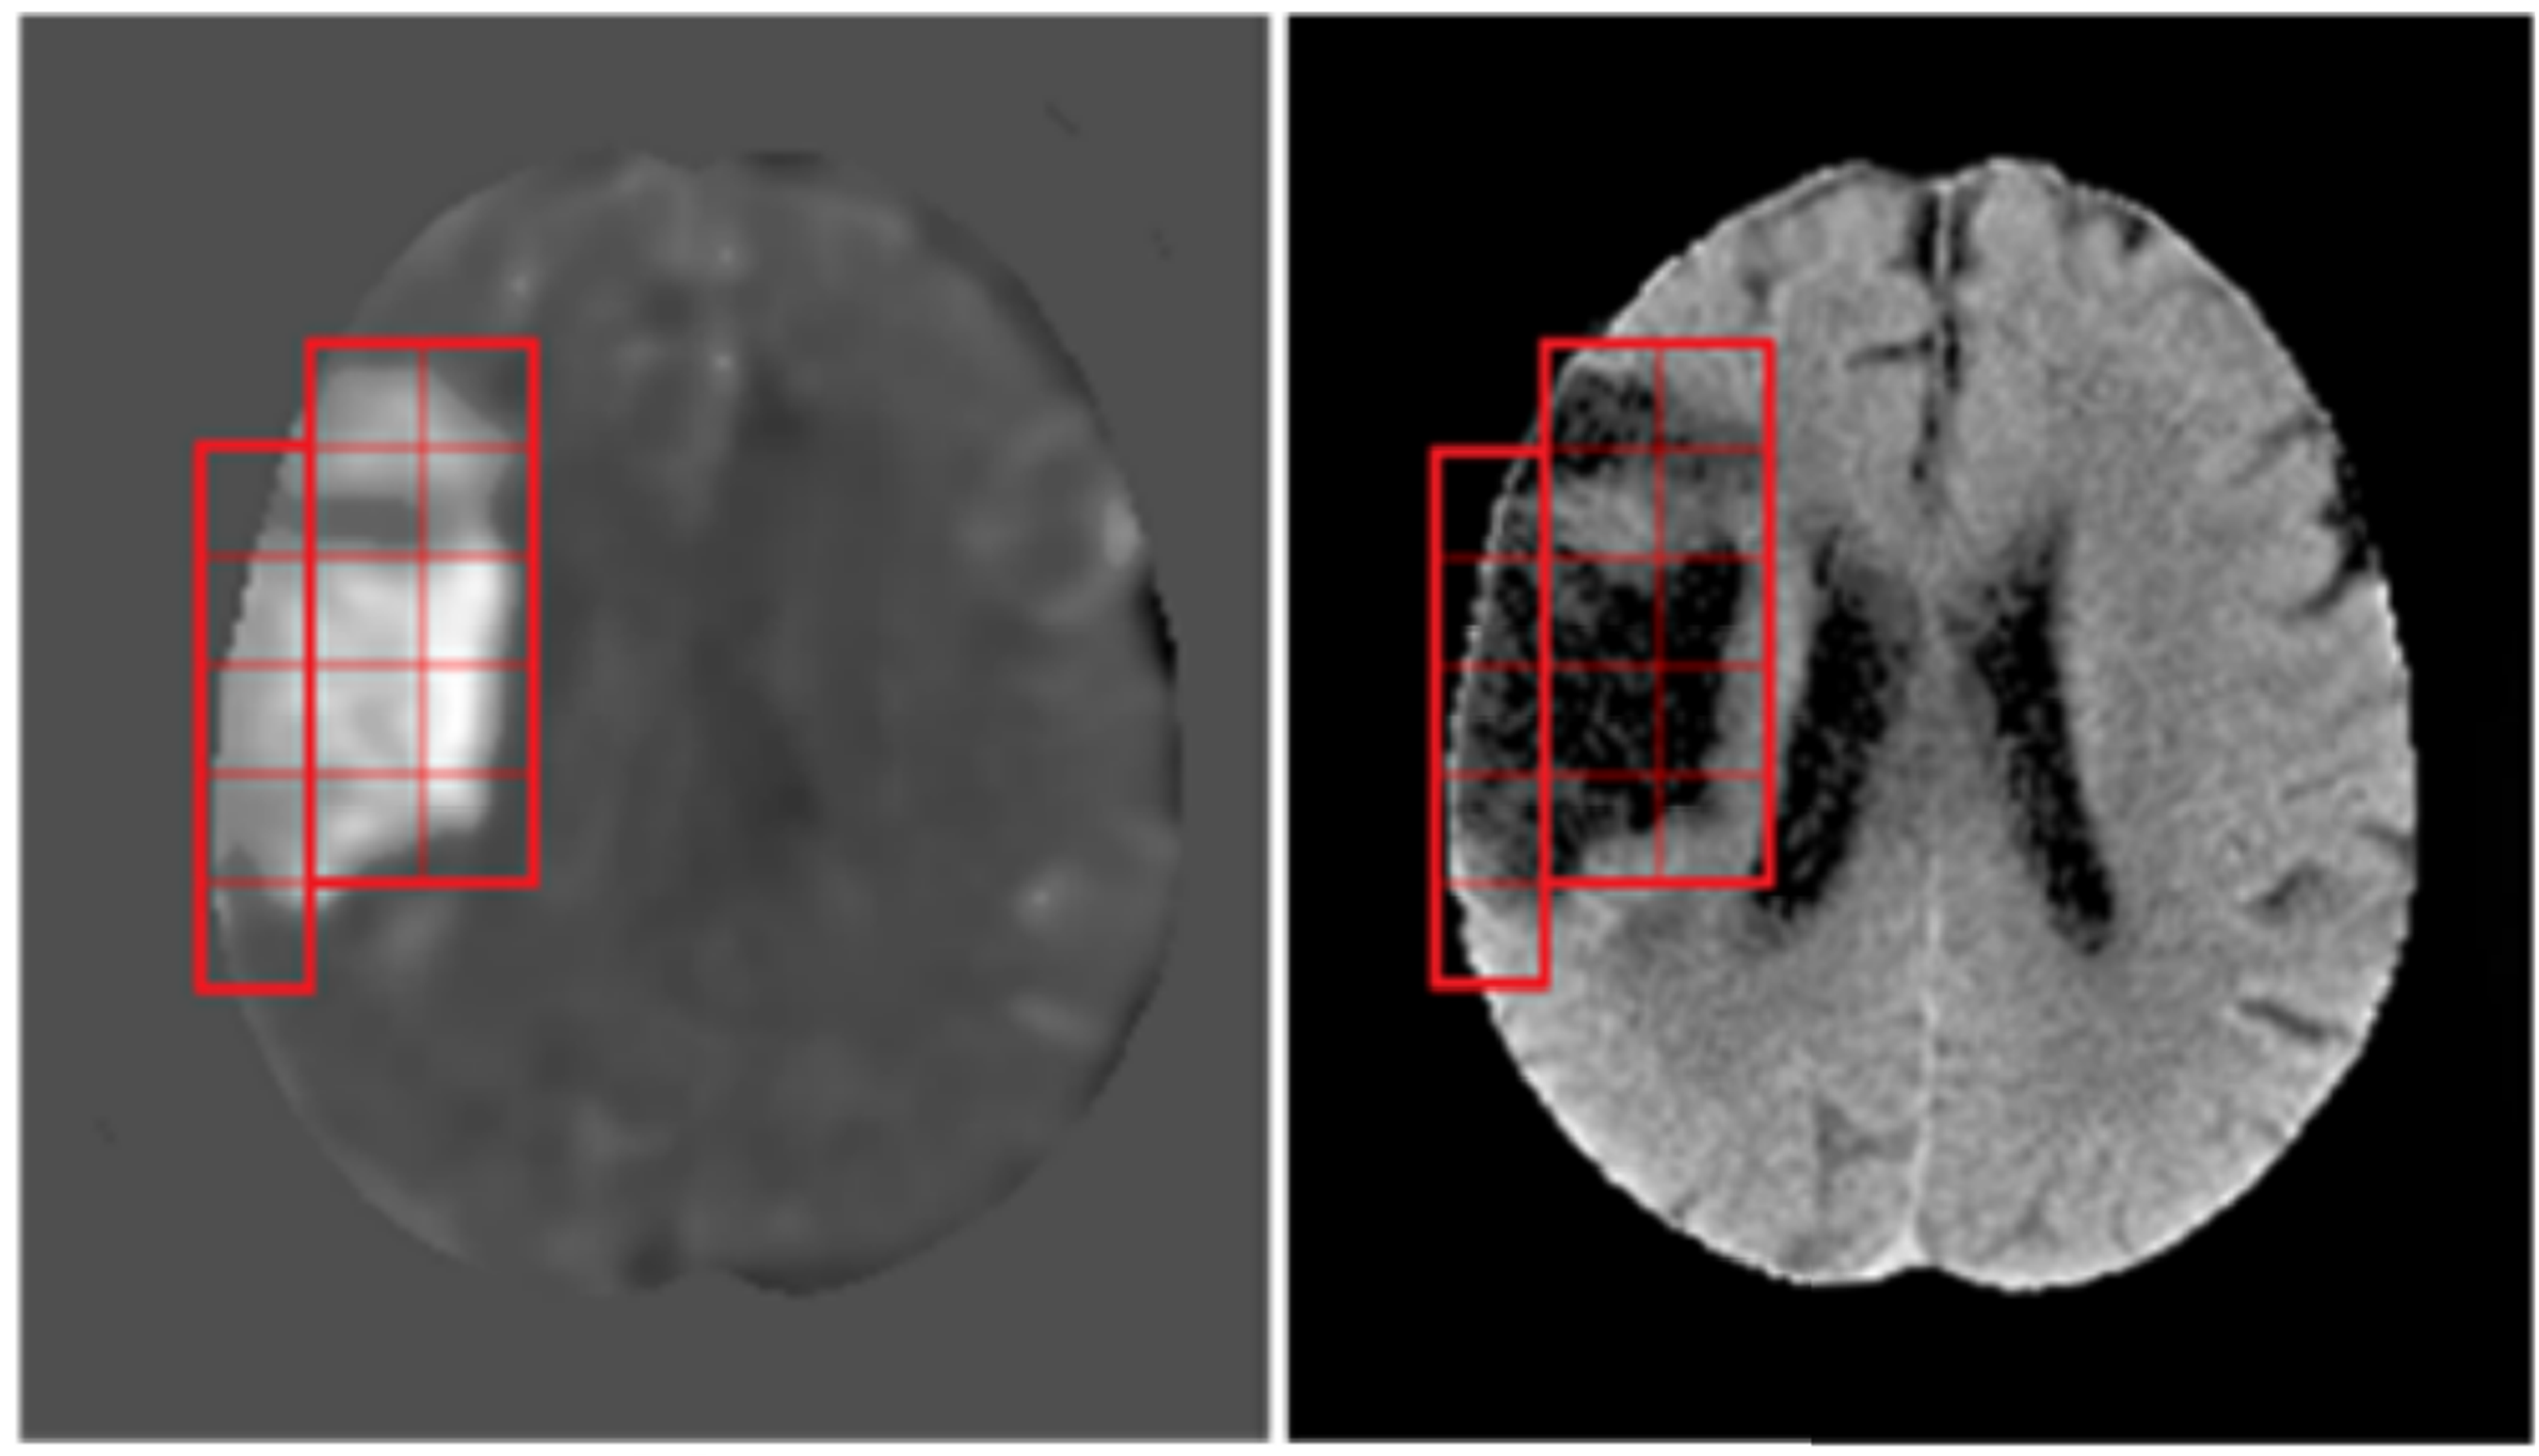

深度學習於腦中風電腦斷層影像缺血區之偵測

蔡章仁

中央大學 電機工程學系副教授

中央與聯新合作中風研究團隊

中央大學 副教授

電機系

技術亮點:

中風病人之快速篩檢